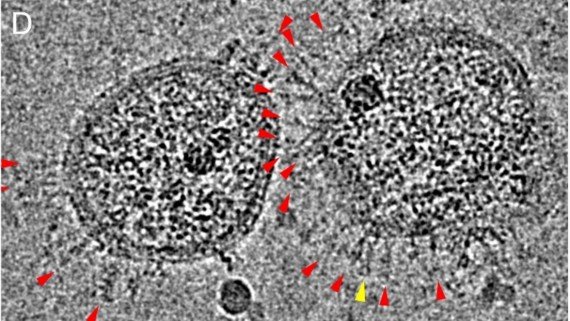

Los científicos estudiaron muestras de sangre de una paciente infectada con el coronavirus de 47 años que había viajado de la ciudad china desde Wuhan, origen de la pandemia, a Australia, que no presentaba patologías previas y que fue puesta en aislamiento, donde logró vencer la enfermedad 13 días después de haberla contraído.